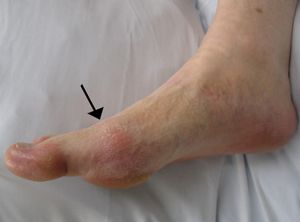

통풍의 가장 흔한 증상은 급성 염증성 관절염의 재발성 발작이다.[1] 해당 관절 부위가 갑자기 붉어지고 붓고 뜨거워지며, 열감이 느껴지고 극심한 통증이 발생한다.[1] 근육이 경직되거나 환부 표면의 피부 표피층이 벗겨지기도 한다. 통증은 찌르는 듯하고 욱신거리는 양상을 보이며, 주로 밤이나 새벽에 시작되어 발병 후 24시간 이내에 최고조에 달한다.[1][38] 이는 주로 밤에 체온이 낮아지기 때문이다.[38] 드물게 피로나 고열이 동반될 수도 있다.[7][15]

급성 통풍 발작은 주로 엄지발가락의 족지절 관절에서 가장 흔하게 발생하며, 전체 환자의 절반가량이 여기에 해당한다.[7] 요산 결정은 비중이 높아 중력의 영향으로 발 부위에 잘 침착되기 때문이다. 그러나 발뒤꿈치, 발목, 무릎, 손목, 손가락 등 다른 관절에도 발생할 수 있으며,[1] 드물게는 여자에게도 나타날 수 있다. 초기 증상은 발 부위인 경우가 많지만, 발목이나 무릎 관절에서 시작되기도 한다. 발가락 뿌리나 아킬레스건 부위에 발작이 오면 통증과 함께 걷기 어려워질 수도 있다.